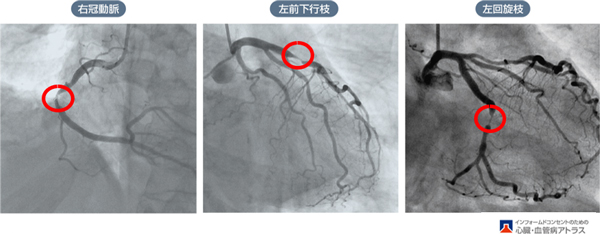

3.冠状動脈

心臓の表面では3本の細い動脈が走行しています。ちょうど心臓が冠をかぶっているかのように見えることから冠状動脈と呼ばれます。この冠状動脈が心臓に血液を送り届けているのです。

冠状動脈には、左冠動脈と右冠動脈の2本があり、左冠動脈はすぐに前下行枝と回旋枝に分かれます。